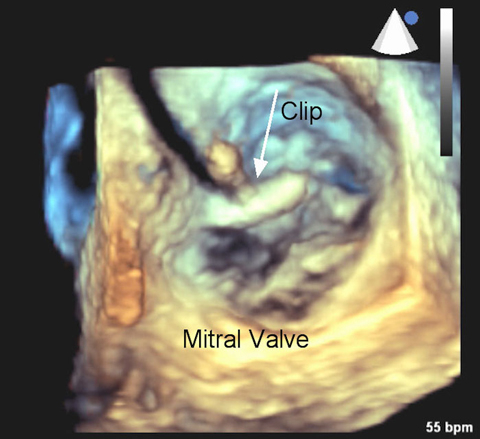

Multidisciplinary Team Performs Minimally-Invasive Transcatheter Mitral Valve Repair